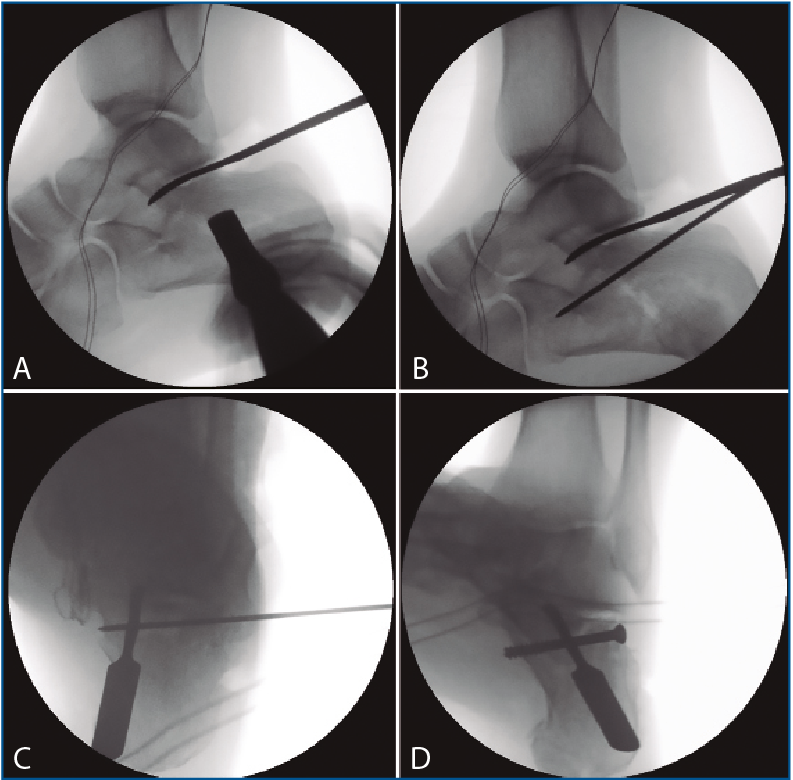

Primero, realizamos limpieza de tejidos blandos y localizamos el flexor hallucis longus (FHL), que será el límite medial de seguridad. Recordamos que, en las fracturas de grado II de Sanders (Figuras 1 y 2), permanece íntegro un gran fragmento anteromedial, mientras que el fragmento posterolateral se desplaza. Tras la limpieza, identificamos la fractura (Figura 3) y movilizamos el fragmento lateral. Luego cambiamos los portales e introducimos el artroscopio por el portal medial, que nos permite acceder hasta el seno del tarso y visualizar el ligamento interóseo talocalcáneo. A través de un pequeño abordaje en la cara lateral del calcáneo reducimos la articulación subastragalina posterior (Figura 4A).

En los 4 casos con osteosíntesis percutánea, una vez levantado el fragmento, se realiza una fijación provisional con agujas de 1,8 mm (Figuras 4B y 4C), que podemos emplear, además, para manipular el fragmento y mejorar la corrección. A continuación, se procede a la inserción de los tornillos canulados de 3,5 mm de lateral a medial, solidarizando el fragmento lateral con el anteromedial (Figura 4D). Se debe combinar la visión artroscópica con una visión radiológica que nos confirme la posición y longitud adecuada de los tornillos.

Figura 4. A: control de escopia intraoperatoria (perfil) de la lesión reducida con ayuda de periostotomos; B: control de escopia intraoperatoria (perfil) tras insertar la primera aguja mientras se mantiene la reducción con un periostotomo; C: control de escopia intraoperatoria (axial de calcáneo) tras insertar la primera aguja mientras se mantiene la reducción con un periostotomo; D: control de escopia intraoperatoria (axial de calcáneo) tras colocación del primer tornillo de osteosíntesis.